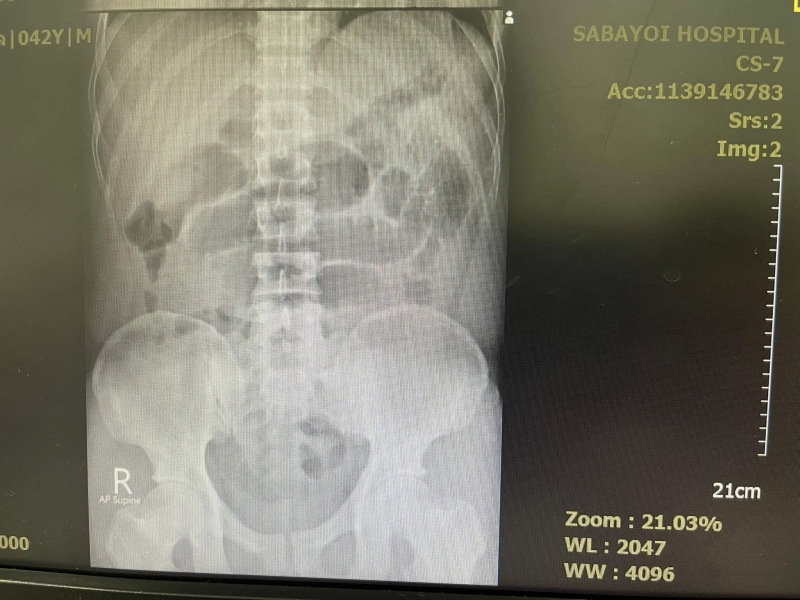

คนไข้อายุสี่สิบเศษ กินน้ำท่อม ทุกวันมา 4-5 ปี ปวดท้องจึงมาโรงพยาบาล ผมคลำแล้วก็พบว่าท้องอืดๆ ให้ไปเอ็กซเรย์ กลับมาภาพสวยเหมือนในตำรา พบว่ามีภาวะลำไส้อุดตัน จึงให้นอนโรงพยาบาลใส่สายยาง NG tube เข้ากระเพาะต่อกับเครื่องดูดลมออกจากกระเพาะ ถ้าดีขึ้นลำไส้คลายตัวก็โล่งไป ถ้าไม่ดีก็ต้องส่งไปผ่าตัด